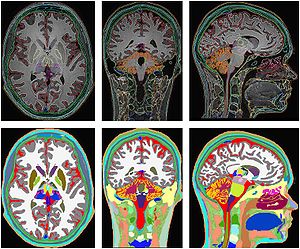

- 1.34 Fully Automated Whole-Head Segmentation with Improved Smoothness and Continuity, with Theory Reviewed

- 1.36 MIDA: A Multimodal Imaging-Based Detailed Anatomical Model of the Human Head and Neck